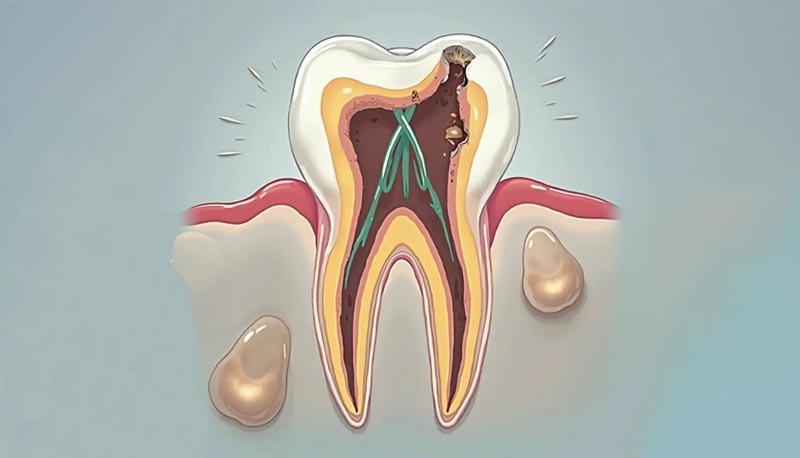

- مرحله چهارم: درگیری پالپ دندان

زمانی که پوسیدگی به مغز دندان (پالپ) برسد، التهاب و عفونت رخ می دهد که معمولاً با درد شدید و ضربان دار همراه است. در این مرحله، بیمار ممکن است به درمان هایی مانند عصب کشی دندان یا در موارد شدیدتر، کشیدن دندان نیاز داشته باشد.

- اگر پوسیدگی به پالپ دندان رسیده باشد، درمان ریشه دندان (Root Canal Therapy) لازم است.

- در این روش، پالپ عفونی خارج شده، کانال های ریشه تمیز و شکل دهی می شوند و سپس با مواد زیست سازگار پر می گردند.

- معمولاً پس از درمان ریشه، برای جلوگیری از شکستگی، از روکش دندانی استفاده می شود.